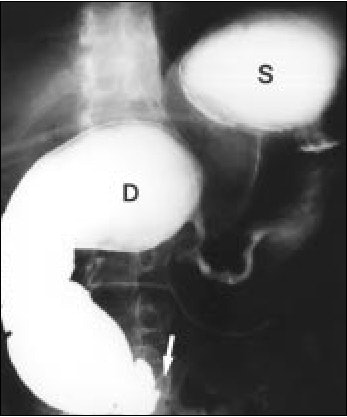

Above, an example of a pyloric channel ulcer (black arrow). Below, a spot compression view. Ulcers are often associated with NSAID usage.

Dr. Sung Eun Rha of the Catholic University of Korea in Inchon, South Korea, documented a case of a duodenal diaphragm associated with long-term NSAID use in a 55-year-old man who had been treated with both NSAIDs and steroids for four years to relieve hip pain due to avascular necrosis (American Journal of Roentgenology, September 2000, Vol. 175:3, pp. 920-921).

For gastrointestinal injuries, the key findings range from a narrowing of the pyloric canal with distension of the duodenum’s first and second portions, fistulae, strictures, and erosions in the esophageal lining. A variety of modalities can document such signs. Rha’s team used delayed-compression spot radiography to document duodenal diaphragm, and confirmed it with exploratory laparoscopy.

| Upper gastrointestinal radiograph shows smooth narrowing of pyloric canal and marked distension of first and second portion of duodenum (D). Also, note marked passage disturbance at third portion of duodenum to distal bowel loops (arrow). S is the stomach. Rha, SE, Lee JH, Lee SY, Park, SM, "Duodenal diaphragm associated with long-term use of nonsteroidal anti-inflammatory drugs: a rare cause of duodenal obstruction in an adult," (AJR 2000, Vol. 175, pp. 920-921). |